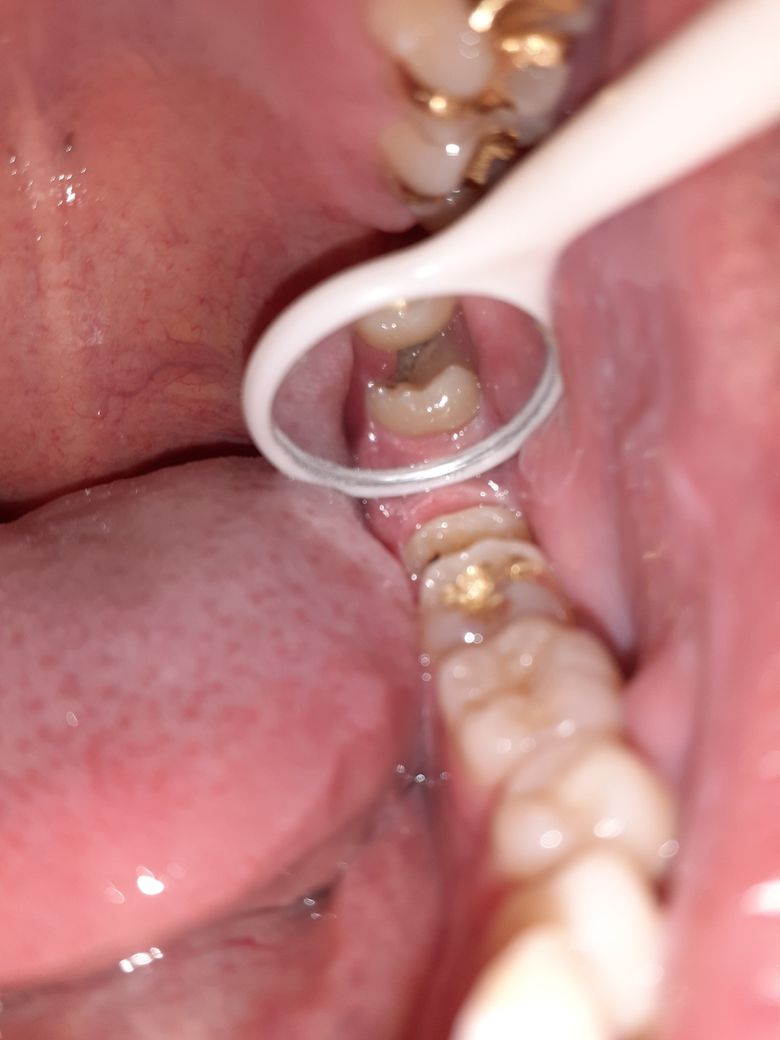

사랑니 부근 잇몸이 이렇게 검게 변하였습니다. 지금도 그렇고 이전에도 그렇고 통증이나 그런거는 없었는데 원인이 무엇인가요?.

• 2번 째 사진